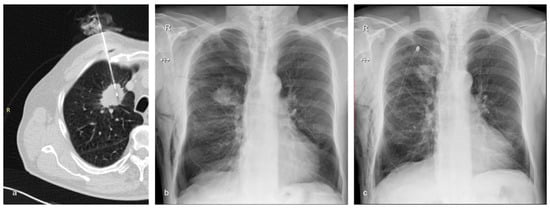

Figure 3.

A 72-year-old man with emphysema and a tumor in the right upper lobe belonging to Group B (the treatment group). The nodule was confirmed to be adenocarcinoma by the histopathological examination. (a) Axial CT showing the 17G coaxial needle and the 18G biopsy needle within the lung mass. (b) Chest X-ray performed 2 h after the biopsy showing moderate post-procedural pneumothorax and subcutaneous emphysema. The patient complained of right chest pain and dyspnea. It was decided to insert a chest tube to prevent further expansion of the pneumothorax and to alleviate the symptoms. (c) Chest X-ray of the same patient following the insertion of the chest drain.